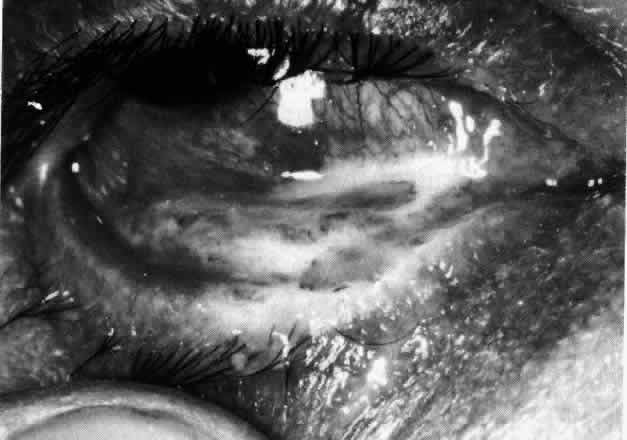

The characteristic features of necrotizing scleritis on fluorescein angiography are hypoperfusion and, eventually, nonperfusion of the vascular networks (Figs. 40 through 43).26 The initial changes are on the venous side of the capillary network; the transit time of the dye increases even if the eye is red and congested. If the disease process persists or has been present for a long time, thrombosis and permanent vaso-occlusive changes occur. These vessels (or the occluded capillary network) are bypassed by the opening of anastomotic channels. New vessels in a granuloma give rise to deep intrascleral leakage of dye (see Fig. 43). Conjunctival and episcleral involvement by the destructive change is late but is always preceded by vaso-occlusive changes that can sometimes be detected with use of the red-free light on the slit lamp (Figs. 44 and 45).

The redness of simple episcleritis may be intense, varying from a fiery-red or a brick-red discoloration to a mild red flush, but it does not have the bluish tinge that is seen in scleritis. The distribution is usually sectorial but can involve the whole anterior segment of the globe. The episcleral vessels are engorged but retain their normal radial position and architecture (Figs. 13 and 14; Color Plate 1A). In simple episcleritis, there is a diffuse edema of the episcleral tissues. These tissues are sometimes infiltrated with gray deposits that appear yellow in red-free light. Surprisingly, the eye is rarely tender to the touch.

In contrast to simple episcleritis, the infiltration and edema of nodular episcleritis are localized to one part of the globe, forming a nodule and some surrounding congestion (Color Plate 1B). The nodule can be moved over the underlying sclera, which is not edematous. The scleral plexus of vessels can be distinguished deep to the nodule, lying flat on the sclera and slightly congested but otherwise normal in color and configuration (Figs. 15 and 16). Episcleral nodules may be single or multiple but do not undergo necrosis (see Fig. 16). After multiple attacks of nodular episcleritis in the same location, the superficial lamellae of the sclera show some alteration and become slightly more transparent in this one area. TREATMENT Even without therapy, simple episcleritis improves considerably within the first week and resolves within 3 weeks (Fig. 17). Provided the eye is not too uncomfortable, most patients can be persuaded to leave the eye untreated, because the condition will resolve spontaneously. However, if it is believed that some treatment is desirable, topical corticosteroids or locally applied nonsteroidal anti-inflammatory drugs (NSAIDs) may make the eye more comfortable and speed resolution slightly (see Fig. 17).9 Use of corticosteroid drops must be continued for several days after the inflammation has subsided to prevent the exacerbation of the condition that occurs if they are stopped suddenly. Prednisolone, betamethasone, or dexamethasone drops may be administered hourly until redness disappears, and then three times daily for 4 to 5 days. Under no circumstances should topical steroids be administered continually for more than a few weeks at a time because of the very real danger of inducing steroid glaucoma and cataract. If the condition fails to respond immediately, other treatment regimens should be sought. Ocular NSAIDs can be administered four times daily until redness disappears. Glaucoma and cataract have not been observed after prolonged use, but many patients become intolerant to the use of the ointment or complain of stinging and irritation. Whereas simple episcleritis resolves rapidly without therapy, the resolution of nodular episcleritis is much slower. Local therapy is consequently of much more value; the same regimen of treatment is followed. In the few patients in whom episcleritis becomes indolent, or in whom recurrences are so numerous that the patient becomes incapacitated, it is reasonable to consider systemic therapy with NSAIDs such as flurbiprofen (Froben), 100 mg three times daily, which usually gives immediate and prolonged relief of symptoms and signs. It is important to note that not all of the NSAIDs work in this condition. Treatment may be terminated abruptly when the condition comes under control. The complications of episcleritis are minor and are not responsible for any decrease in visual acuity. COURSE AND PROGNOSIS Whether treated or not, simple episcleritis will resolve in 10 to 21 days. It will usually reappear at irregular intervals and then eventually disappear. An accurate 12-month record kept by a patient who went without treatment is shown in Figure 18. He was free from any further attacks for 3 years. He then had four attacks in the next 3 months and has had none since. No etiologic or precipitating factor has been found. In nodular episcleritis, the nodule initially increases rapidly in size, sometimes reaching the size of a split pea. Thereafter it gradually regresses over a variable period and eventually disappears, although this may take up to 2 months without treatment. Recurrences occur also in nodular episcleritis, but the two varieties are not mutually exclusive (a simple episcleritis may recur as a nodular episcleritis and vice versa). However, episcleritis never develops into scleritis in the same attack, although it invariably accompanies scleritis. Of 180 patients initially diagnosed as having episcleritis, only 4 developed scleral involvement.10 Episcleritis is an entirely benign condition, although it may be a great nuisance to the patient. It may recur over a period of many years, but it rarely leaves any residual ocular changes except for some areas of scleral transparency or localized stromal keratitis in those patients who have had severe attacks of nodular disease occurring always at the same site. Of 180 patients analyzed,10 only 2% had a decrease in visual acuity of two lines or more within a year of the onset, and in every case this was from increasing involutional cataract. |